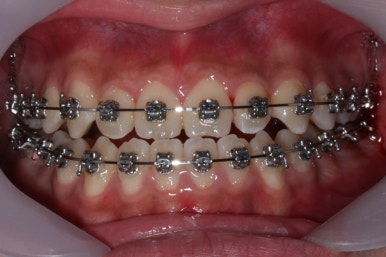

위 사진들은 부산주걱턱교정 키다리아저씨치과에 내원하셨을 당시의 입안 모습입니다.

입 안의 모습에서도 주걱턱의 특징으로는

하악이 앞으로 나와있습니다.

윗니는 뻐드러지고 아래 앞니는 뒤쪽으로 쓰러져 있습니다.

교합이 맞지 않습니다.